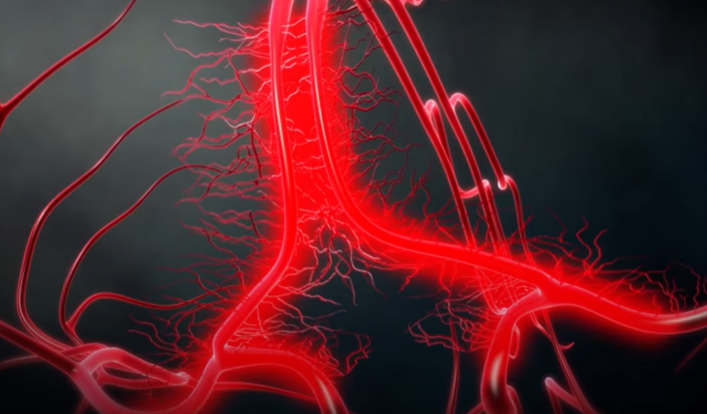

4. 갑자기 뇌혈관이 좁아지는 가역적 뇌혈관 수축 증후군과,

5. 부족한 혈류량을 보충하기 위해 주변으로 가느다란 혈관이 생겨나는 모야모야병